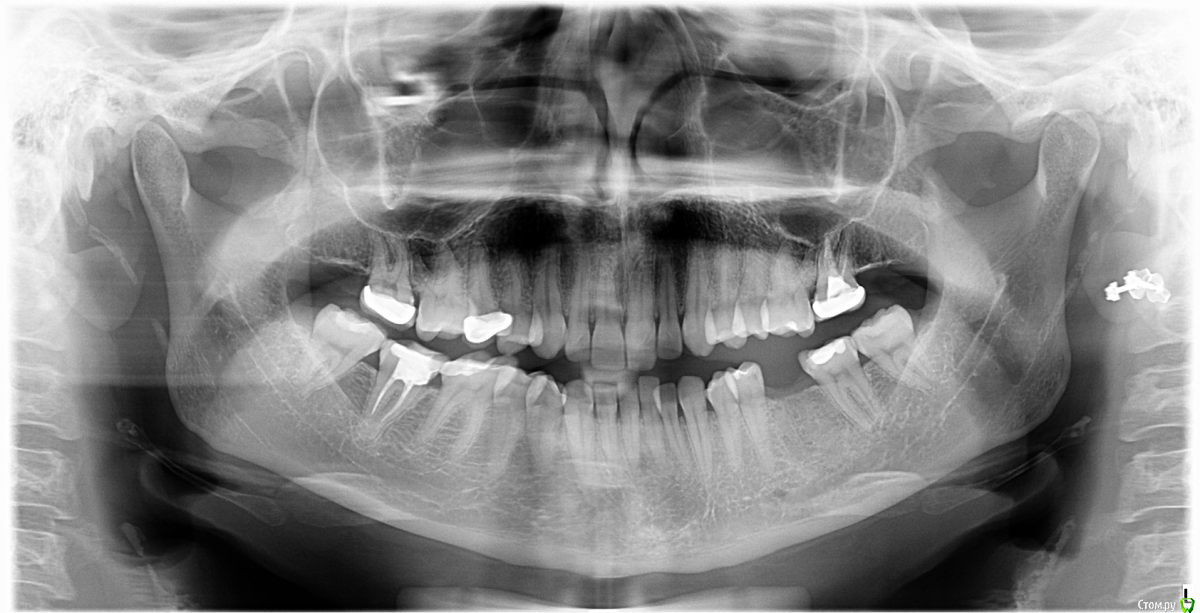

Iam_Yulia Опубликовано 25 ноября, 2020 Поделиться Опубликовано 25 ноября, 2020 (изменено) Доброго дня! Хочу определиться с планом лечения (порядком действий)В прошлом году в августе была удалена нижняя шестерка, хочу поставить имплант.Оказалось, что мне необходимо (желательно?) сначала исправить прикус. Я так понимаю, если решаюсь на ортодонтию, то сначала потребуется удалить обе восьмерки? сделать лечение и коронку (временную) на семерку, так как она почти разрушена? и потом начинать исправление прикуса? А уже после(через какое время?) ставить имплант? Так же я планирую беременность в следующем году (в ближайший год). Те специалисты, с которыми я уже общалась, говорят, что можно совмещать брекеты и беременность. Не лучше лучше ли отложить ортодонтическое лечение на период после окончания грудного вскармливания или я потеряю время? Снимок прилагаю. Есть еще КТ обеих челюстей на диске.Сейчас нахожусь в поиске стоматолога и ортодонта в Москве.Спасибо! Изменено 25 ноября, 2020 пользователем Iam_Yulia Ссылка на комментарий

Brigita Опубликовано 25 ноября, 2020 Поделиться Опубликовано 25 ноября, 2020 Добрый день.Порядок такойСначала очная консультация ортодонта, нужно ли удалять 8ки или нет по снимку определить невозможно. Затем лечение - по снимку я вижу нижнюю правую 6ку, которую надо лечить, если планируете ортодонтическое лечение - то временная коронка. Возможно при очном осмотре и кт обнаружатся и другие "проблемные" места.При планировании будущей беременности в самое ближайшее время, брекеты лучше не ставить. Если готовы подождать с беременностью, то обсудите с ортодонтом сроки лечения - возможно Вы все успеете.После окончания ортодонтического лечения, за 2 месяца до снятия брекетов устанавливается имплант. Если нужна костная пластика, то сначала ее, через несколько месяцев - имплант. Возможен вариант одномоментной пластики и имплантации - нужен осмотр имплантолога и кт. Ссылка на комментарий

Iam_Yulia Опубликовано 27 ноября, 2020 Автор Поделиться Опубликовано 27 ноября, 2020 Добрый день.Порядок такойСначала очная консультация ортодонта, нужно ли удалять 8ки или нет по снимку определить невозможно. Затем лечение - по снимку я вижу нижнюю правую 6ку, которую надо лечить, если планируете ортодонтическое лечение - то временная коронка. Возможно при очном осмотре и кт обнаружатся и другие "проблемные" места.При планировании будущей беременности в самое ближайшее время, брекеты лучше не ставить. Если готовы подождать с беременностью, то обсудите с ортодонтом сроки лечения - возможно Вы все успеете.После окончания ортодонтического лечения, за 2 месяца до снятия брекетов устанавливается имплант. Если нужна костная пластика, то сначала ее, через несколько месяцев - имплант. Возможен вариант одномоментной пластики и имплантации - нужен осмотр имплантолога и кт.Добрый день! Большое спасибо, что ответили. Я была на консультации у ортодонта, врач сказала что восьмерки надо удалять, и что через ориентировочно 4 месяца после начала ортодонтического лечения можно будет поставить имплант, а всего срок лечения около 1,5-2 года. При этом она сообщила что беременность не является противопоказанием к установке БС. (Я читала, почему многие врачи не советуют ставить брекет системы во время беременности, поэтому сомневаюсь)Так же я была у имплантолога на консультации, он сказал, что на данный момент костной ткани достаточно для имплантации, так же сказал что есть показания к исправлению прикуса и желательно делать имплантацию после ортодонтического лечения. Я бы хотела исправить прикус, а уже потом делать имплант, но вот 2 года откладывать планирование беременности я не готова (мне 32) Мой стоматолог (из другого города, у которого я лечилась на протяжении многих лет) посоветовал установить БС после беременности через год. Есть еще вопрос, если я все-таки решаю отложить ортодонтическое лечение, стоит ли мне заранее удалить 8-ки? (одна из них поражена кариесом сильно со стороны десны) и поставить коронку на 6-ку? Можете ли вы посоветовать врача ортодонта и имплантолога в Москве? Спасибо! Ссылка на комментарий